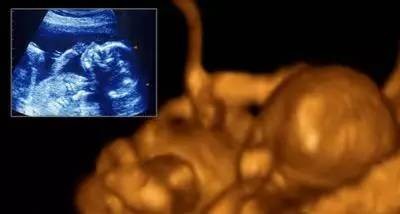

第三个月

胎宝宝和上个月相比,生长迅速,器官也开始工作。头占整个身体的近一半。生殖器发育已经可初步辦认出性别了。通过B超可以观察到胎宝宝四肢活动,肾脏、输尿管形成,可以排泄了。